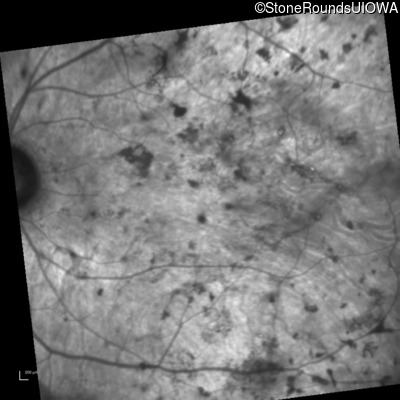

Infrared Fundus Photograph - Right - No Light Perception

Exemplar

Infrared Fundus Photograph - Left - Light Perception